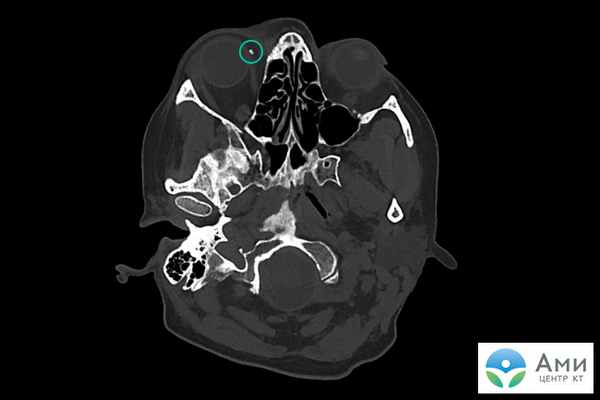

Кальцинат

Кальцинаты — патологические, как правило шарообразные, скопления солей кальция в тканях и органах. На сканах компьютерной томографии визуализируются как белые точки. Небольшие конкрементоподобные новообразования в молочной железе, легких, мягких тканях, артериях в большинстве случаев не причиняют дискомфорт и являются «случайными находками» на КТ, УЗИ, маммографии.

Кальцинаты не опасны, поскольку сами по себе не являются злокачественным новообразованием, однако могут быть «маркером» онкологического процесса, поскольку для очагов кальцификации характерна локализация рядом с опухолью и метастазами. Даже единичный кальцинат, обнаруженный на КТ, может требовать дополнительного обследования, если рядом имеется подозрительное уплотнение.

Размеры кальцинатов варьируются от 1-2 мм (гранулярные, микрокальцинаты, кальцинаты) до крупных (макрокальцинаты). Макрокальцинаты почти всегда доброкачественны и не требуют дальнейшего наблюдения.

Кальцинаты на КТ визуализируются даже при самом небольшом размере капсулы (около 1 мм).